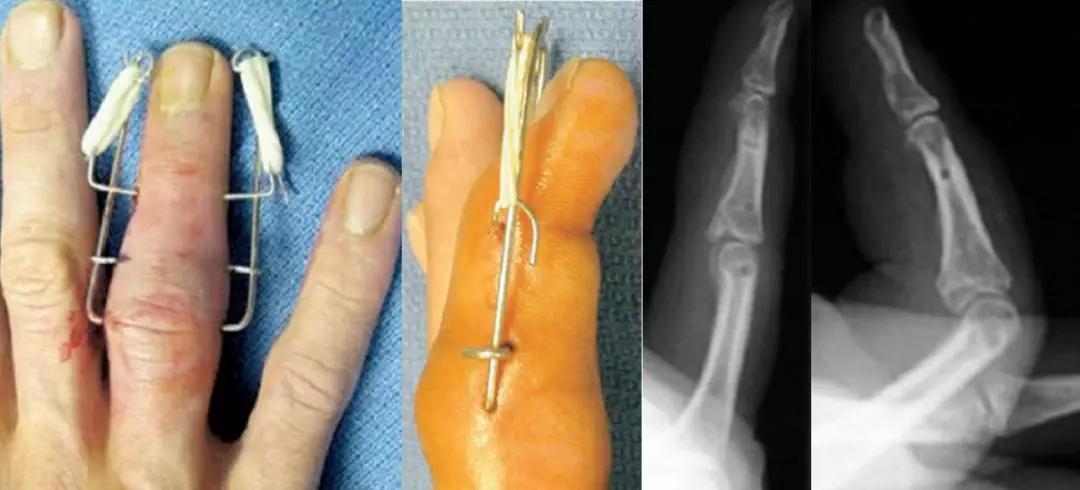

克氏针的n种神奇用法

术中我们仅用了最简单的材料,仅几枚克氏针就完成了这个复杂的手术.

外露克氏针取出图解

外露克氏针取出图片

克氏针图片

外露克氏针图片